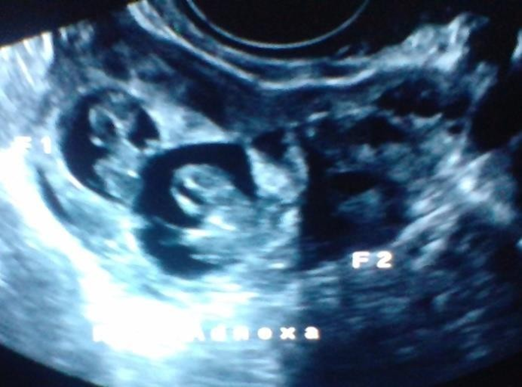

Ultrasonography with doppler study showed a uterus of 8.3x 5.4x 4.2 cms with endometrial thickness of 10 mm and there was evidence of large heterogeneous lesion in the right adnexa of a size 7.1x 5.1 cms, with sac like structure within which two foetal poles measuring 1.4 cm = 7 weeks and five days .Fetal cardiac activity was appreciated .Mild free fluid was seen in the abdomen. An impression of live twin ectopic pregnancy in the right adnexa was made with mild free fluid in an abdomen. A pseudosac like structure was noticed in endometrial cavity .Both ovaries were visualised separately from the right adnexal mass.

Figure1:Shows Right adnexal sac with Twin live ectopic gestation of approximately 7wks 5 days .No intrauterine pregnancy .Both ovaries are separately visualised.